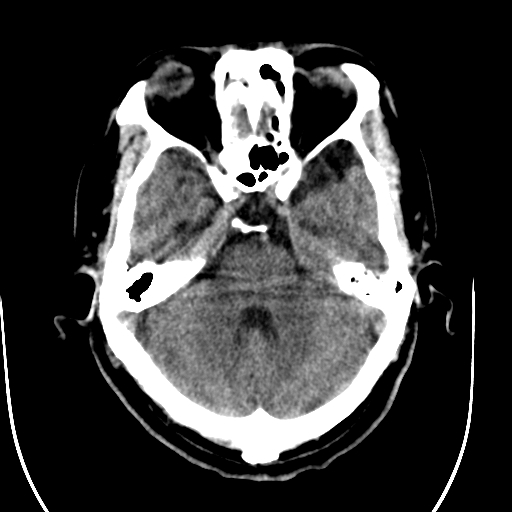

标题: CT28335:男,58岁,请各位看看是不是有脑积水,蝶窦内高密 [打印本页]

标题: CT28335:男,58岁,请各位看看是不是有脑积水,蝶窦内高密

轻度积水,蝶窦正常。

1)脑积水。2)副鼻窦炎。